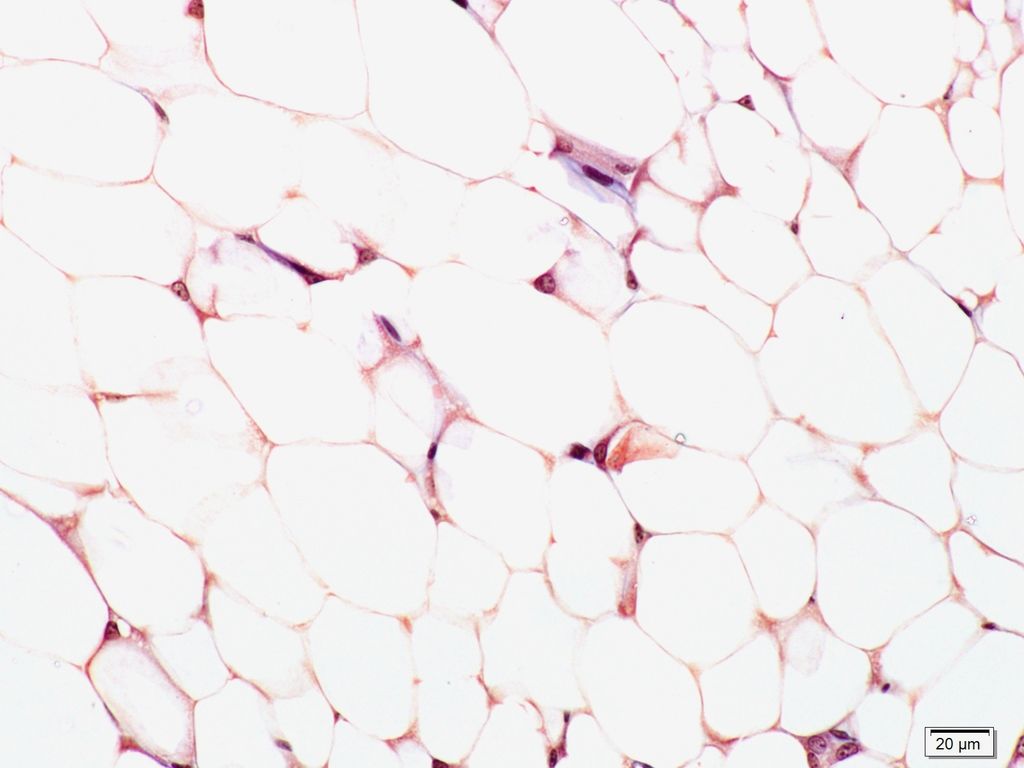

Question 3

Question

Identifiez le type de tissu conjonctif (en h à g) ainsi que l'organe où l'on se trouve (en h à d) et les structures pointées :

Answer

• tissu adipeux mature ou graisse blanche

• gouttelette lipidique

• noyau adipocyte

• hypoderme